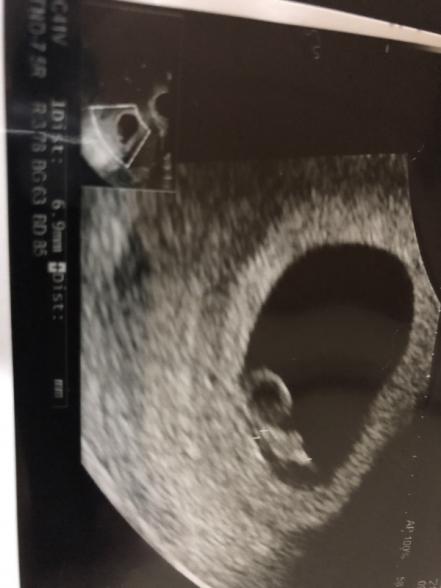

妊娠7週目

心拍も確認は出来ています。7週で1cmが多いのではと心配です

・大きさは頭殿長(とうでんちょう)約1㎝程度

・重さは4g (さくらんぼ1個分)

・心拍が確認できる

この中で一番重要なのは、心拍の確認ができること。確かに赤ちゃんの身長は約1cmほどと言われていますが、毎日毎日大きくなる時期ですから、今は見守っていきましょう。

頭と胴は分かれ、手と足も分かれて二頭身の人間らしい形になってきますよー!脳や脊髄の神経細胞の約8割が完成してきます。